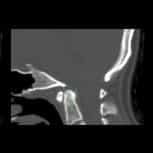

我們是一家位於西班牙巴塞隆納的國際專科醫療中心,不設分院,專注於精準且高品質的醫療照護。我們採用微創手術從病因治療Arnold-Chiari I型症候群、特發性脊髓空洞症與脊柱側彎等相關疾病,致力於為來自世界各地的患者帶來更安全、更有效的治療選擇。